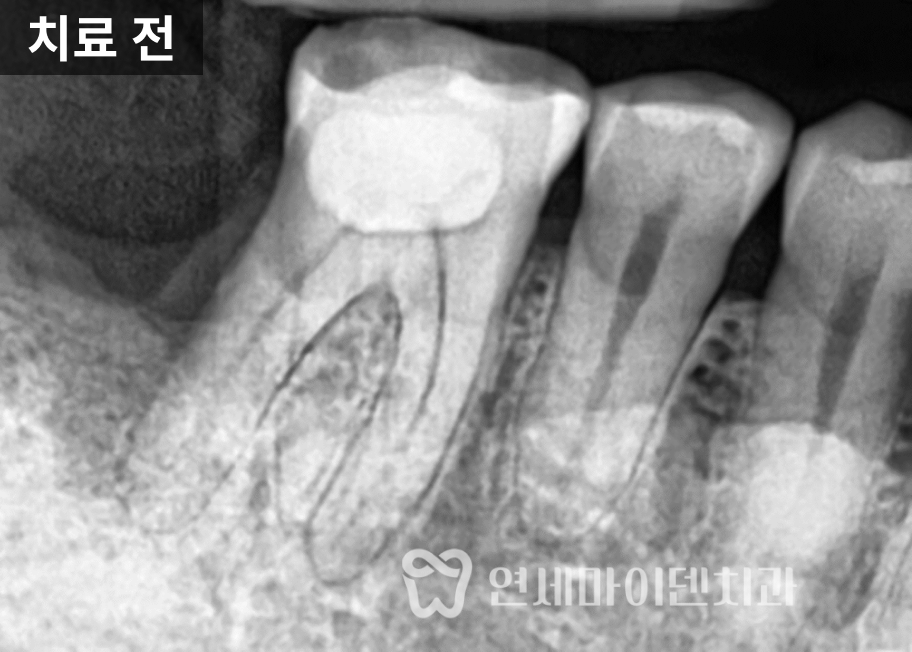

저희 병원에 재치료를 받으러 오신 사례입니다.기존 임플란트 실패 원인 분석

이 환자분은 한 달 전에 타원에서

임플란트를 식립 받으셨지만,불과 한 달만에 임플란트가 빠져서

저희 병원을 찾아오셨습니다.구강 내 상태를 확인하고

CT 촬영을 진행한 결과,

해당 부위는 골밀도가 낮았고

염증이 완전히 해소되지 않은 상태였습니다.또한 기존에 시행된

뼈이식 재료 역시

안정적으로 정착되지 못한 모습이

확인되었습니다.이러한 상황이라면

처음부터 발치 즉시 임플란트를

진행하기보다는,감염 부위를 충분히 제거하고

치조골 회복을 유도한 뒤

안정적인 환경에서 식립을 고려했어야 합니다.

또 하나 주목할 점은

픽스처 위에 힐링 어버트먼트가

이미 연결된 상태였다는 점입니다.고정력이 충분히 확보되지 않은 상태에서

힐링 어버트먼트를 연결하면

픽스처에 지속적인 힘이 전달되고,

이로 인해 임플란트 실패로

이어질 가능성이 높아집니다.실제로 이 케이스에서는

픽스처가 단단히 고정되지 않은 상태였고,

결과적으로 식립 후

한 달 만에 임플란트가 탈락하게 되었습니다.임플란트 재수술 과정

골밀도는 점차 회복되었고,CT 상에서도

염증이 있었던 부위가

하얗게 변화하며

뼈의 재형성이

잘 이루어지고 있음을 확인할 수 있었습니다.